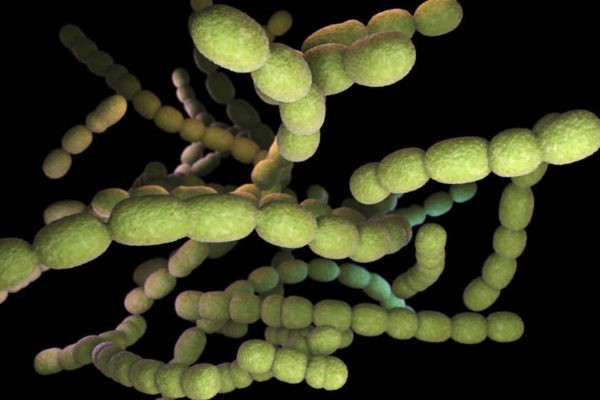

Какие микроорганизмы обычно вызывают пневмонию?

Самый частый возбудитель пневмонии – это стрептококк. С ним связана классическая тяжелая пневмония, с высокой температурой, и сильной слабостью. Стрептококк встречается и у молодых и у пожилых пациентов, у курящих и некурящих людей. Практически так же часто встречается микоплазменная пневмония. Особенно часто она встречается у детей школьного и дошкольного возраста, молодых людей, которые учатся в институте или уже работают. Особенностей этой пневмонии является неявные симптомы и распространение среди людей, посещающих одно учреждение.

Реже пневмония связана с хламидийной инфекцией. У курильщиков часто встречается пневмония, вызванная гемофильной палочкой или бактерией вида моракселла. Стафиликокк часто встречается у наркоманов или при наличии очагов гнойной инфекции (например, пролежни). У лиц, употребляющих алкоголь, а также среди больных диабетом может встречаться клебсиелла.

У пациентов с тяжелой хронической обструктивной болезнью легких, а также с бронхоэктазами может встречаться инфекция синегнойной палочкой. У лежачих больных, за которыми требуетcя постоянный уход, у которых стоит мочевой катетер, может встречаться инфекция кишечной палочкой или энтеробактерией. При иммунодефиците, в частности при СПИДе, повышается риск пневмоцистной пневмонии, грибковой пневмонии и туберкулеза. Знание особенностей формирования пневмонии позволяет врачу быстрее поставить правильный диагноз и вовремя начать лечение.